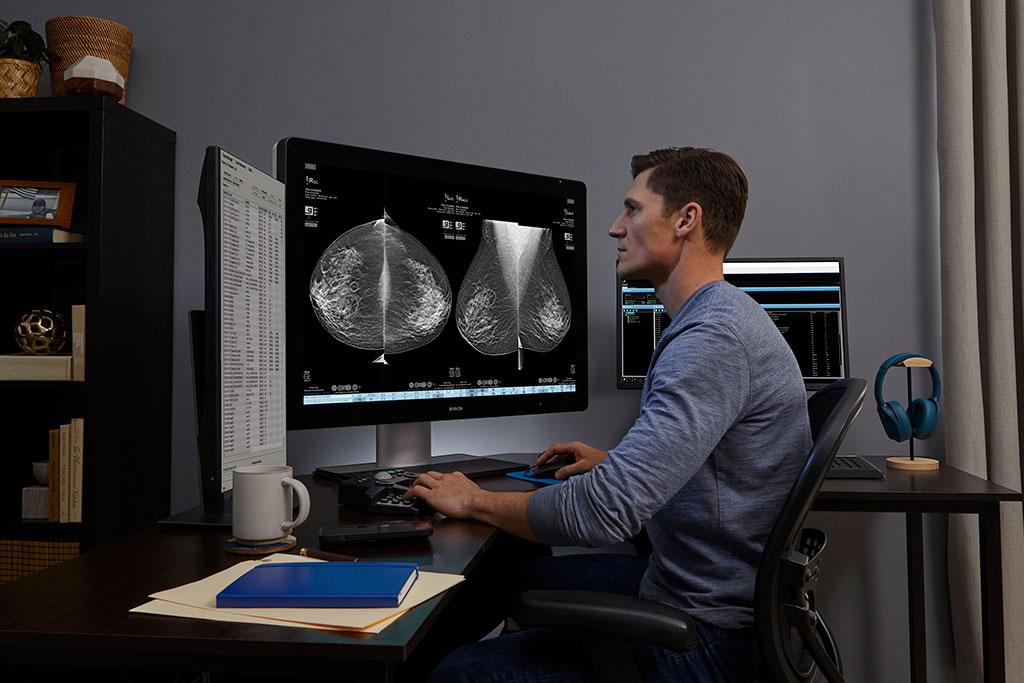

Enhancing reading productivity with the right tools.

SecurView breast imaging workstations are built with the specific needs of breast radiologists in mind. The SecurView 12.0 solution provides advanced, customizable workflows and cutting-edge image manipulation tools to ensure accurate, efficient evaluation, with the added flexibility of fully accessible remote viewing.

Enhancing Efficiency, in the Reading Room and at Home